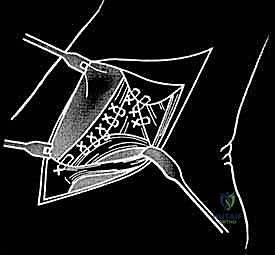

الخطوة الثالثة: الشق الجراحي والوصول الآمن

يتم عمل شق جراحي دقيق ومدروس على الجانب الداخلي للكاحل، خلف وتحت الكعب الإنسي. يستخدم الدكتور هطيف تقنيات تشريحية دقيقة لحماية الهياكل الحيوية المحيطة، وخاصة العصب الصافن (Saphenous Nerve) والوريد المرافق له، لتجنب أي تنميل أو ألم عصبي مزمن بعد الجراحة.

الخطوة الرابعة: تقييم وإصلاح رباط الدالية (Repair vs. Reconstruction)

بمجرد الوصول إلى رباط الدالية، يتم تقييم درجة التلف:

* الإصلاح المباشر (Direct Repair): إذا كانت أنسجة الرباط الممزقة ذات جودة جيدة (عادة في الإصابات الحديثة)، يقوم الدكتور هطيف بخياطتها مباشرة. يستخدم خطاطيف تثبيت عظمية (Suture Anchors) صغيرة جداً ومصنوعة من مواد متوافقة حيوياً (تذوب مع الوقت أو من التيتانيوم) لغرس الخيوط القوية في عظمة الكعب الإنسي، ثم يتم سحب الرباط الممزق وتثبيته بقوة في مكانه التشريحي الأصلي.

- إعادة البناء (Reconstruction): في الحالات المزمنة حيث يكون الرباط الأصلي قد تليف، تآكل، أو أصبح غير كافٍ للاستخدام، يلجأ الدكتور هطيف إلى تقنية "إعادة البناء". تتضمن هذه التقنية المتقدمة استخدام رقعة وترية (Graft)، إما من جسم المريض نفسه (Autograft - مثل أوتار الركبة أو وتر من القدم) أو رقعة صناعية متطورة. يتم حفر أنفاق ع